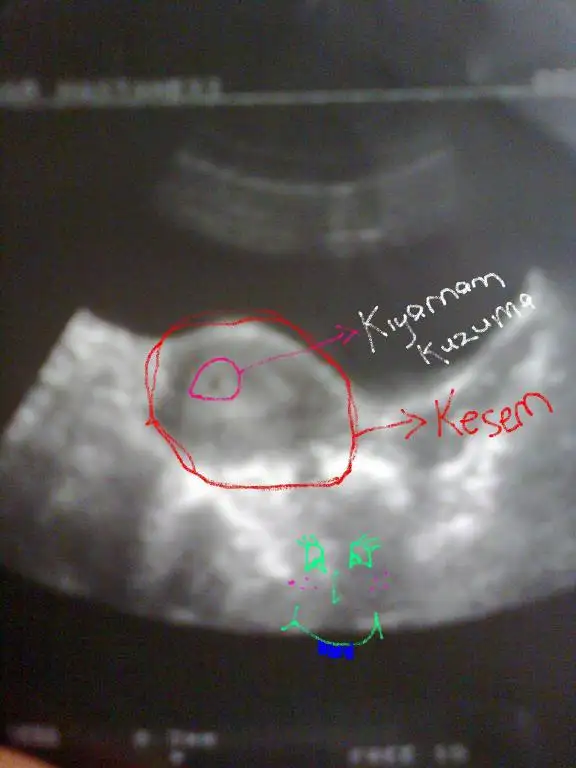

Hülya dün face e yazdı hastanede beklerken telefondan bağlanmıştı kesesi düzgündü. ama bebeği görememişti. bende göremedim mesela. demmir sen ile aramızda 2 gün var sanırım ama sende nokta bile vardı mesela. kişiden kişiye değişiyor galiba.

evet canım benim de bebek falan yoktu dediğin gibi sadece nokta vardı, bakalım ben gidince ne görücem.

canım ben 6+4 te gördüm birinin kalp atışını da duydum ama diğeri daha küçüktü onun kalp atışını göremedik bana vajinal baktı o yüzden gördüm çünkü 5+6da başka doktora gittiğimde kesleri anca görmüştük karından bakınca ; vajinalla karında bakması arasında rahat bir hafta oynuyor endişelenme sakın hepimiz sağlıkla bebeklerimizi kucağımıza alacağız inşallah

maşallah maşallah bu benım ilk düzgün kesem sac 6.3 mm yanı bebeğim olusmaya baslmaıs 10 gun sonra kalp sesı duymayı beklıyoruz ınsallah... :)